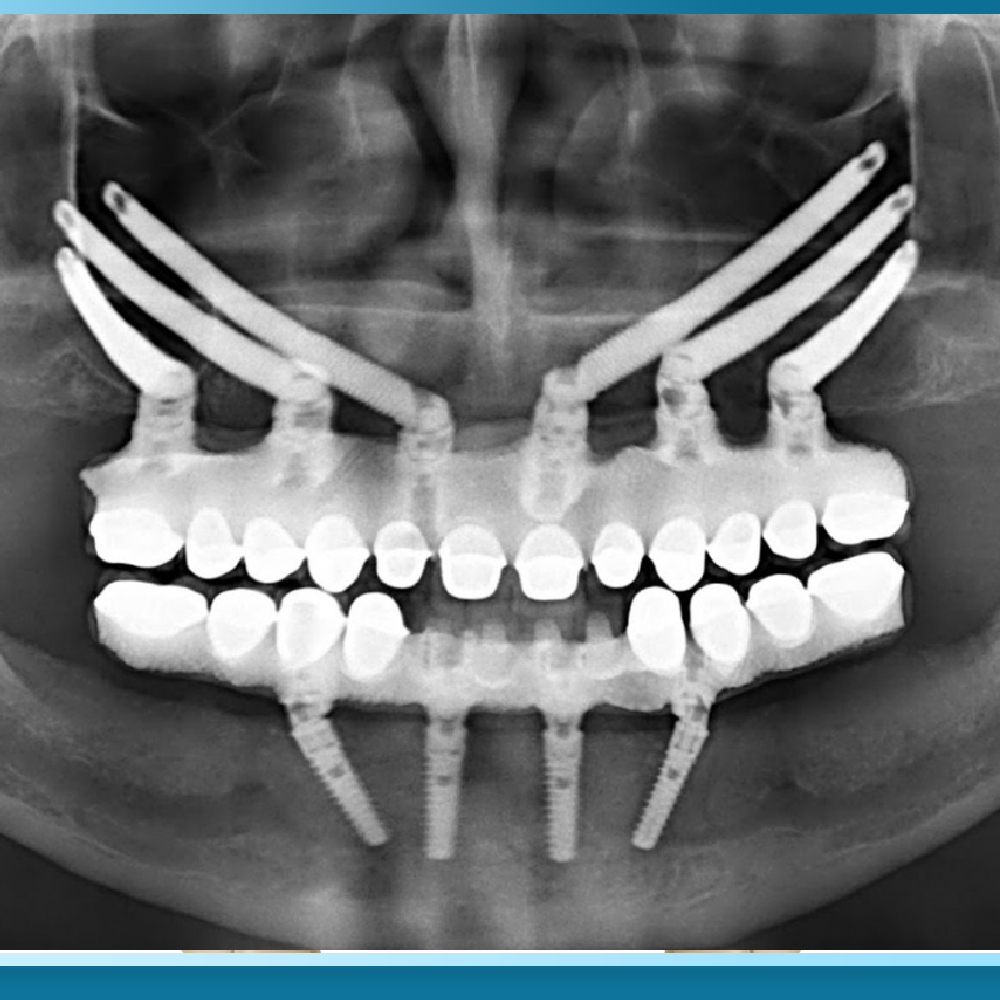

Kỹ thuật này sử dụng các trụ Implant có thiết kế đặc biệt với chiều dài vượt trội, thường dao động từ 30mm đến 50mm, gấp 3 đến 4 lần so với các loại trụ thông thường để xuyên qua vùng xương hàm đã tiêu biến và neo giữ trực tiếp vào xương gò má.

Xương gò má có đặc tính sinh học rất quan trọng là mật độ xương cực kỳ cứng chắc và hầu như không bị tiêu biến theo thời gian, ngay cả khi bệnh nhân bị mất răng lâu năm hoặc mắc các bệnh lý về xương hàm. Khi kết hợp với phác đồ All on 6, bác sĩ sẽ cấy ghép từ 2 đến 4 trụ Implant gò má ở vùng răng sau, kết hợp với các trụ Implant thông thường ở vùng răng cửa phía trước để tạo thành một hệ thống nâng đỡ vững chãi.

Sự kết hợp này cho phép phân bổ lực nhai đều khắp cung hàm, đảm bảo tính bền vững và an toàn cho hàm phục hình sứ bên trên. Phương pháp này đòi hỏi sự tính toán chuẩn xác về giải phẫu học để tránh tác động đến các cấu trúc nhạy cảm như xoang hàm hay hốc mắt.

Quy trình chẩn đoán cho ca Implant gò má đòi hỏi sự hỗ trợ từ các công nghệ hình ảnh tiên tiến nhất. Bác sĩ cần sử dụng phim CT Cone Beam 3D để khảo sát toàn bộ cấu trúc xương gò má, xoang hàm và các dây thần kinh liên quan.

Việc lập kế hoạch điều trị thường được thực hiện trên các phần mềm giả định 3D chuyên dụng để xác định chính xác góc nghiêng và vị trí điểm neo của trụ.